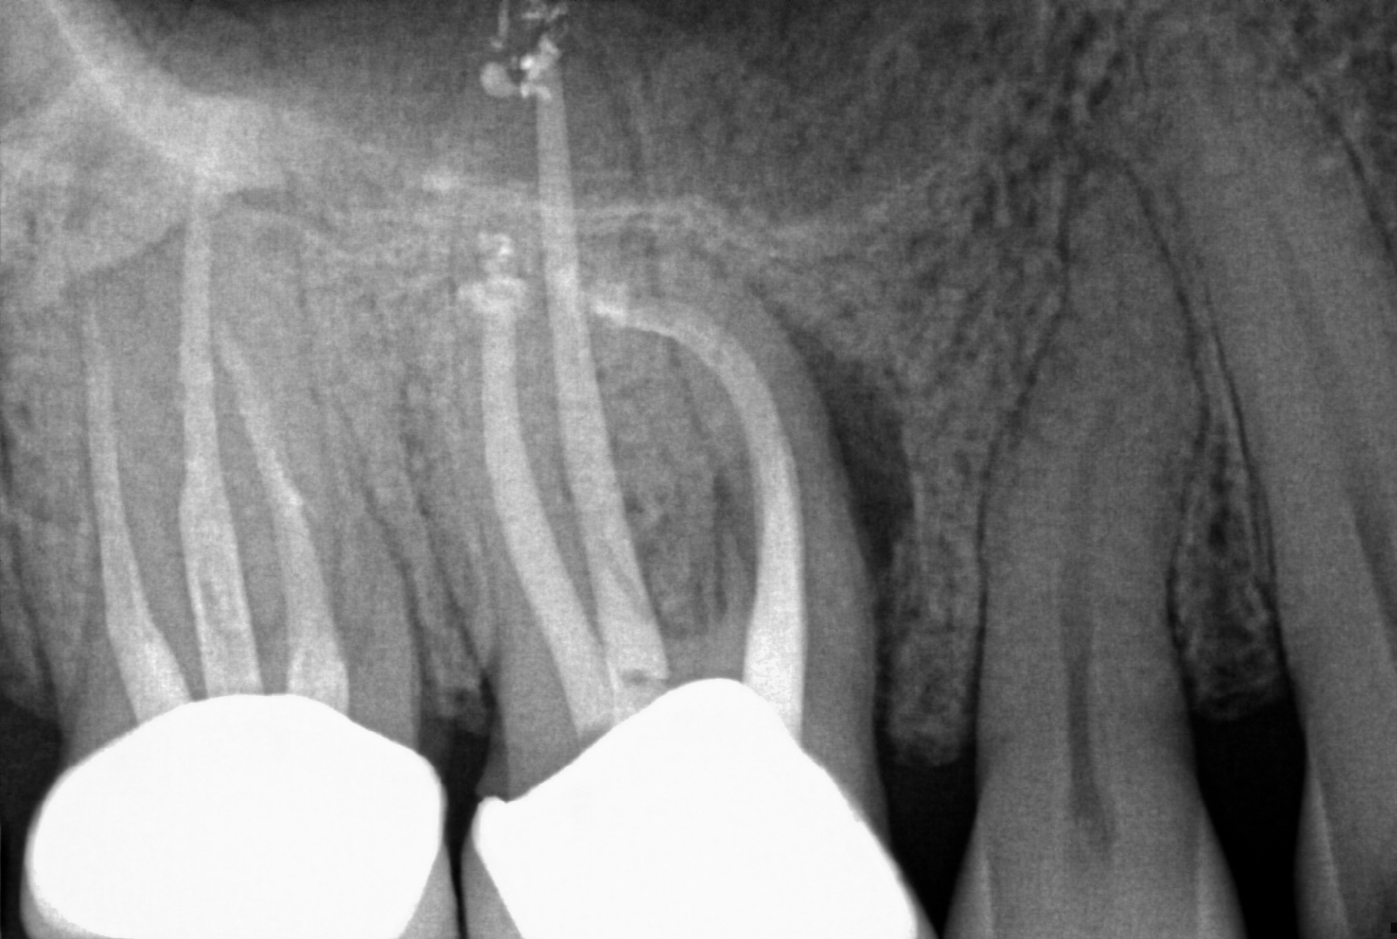

Resorption

Resorption is a condition where the tooth’s structure starts to break down, either from the inside out or from the outside in. It can be caused by trauma, inflammation, or other factors. Endodontic treatment for resorption involves removing the damaged tissue and reinforcing the tooth with materials that help prevent further damage. The aim is to save the tooth and maintain its functionality as much as possible.